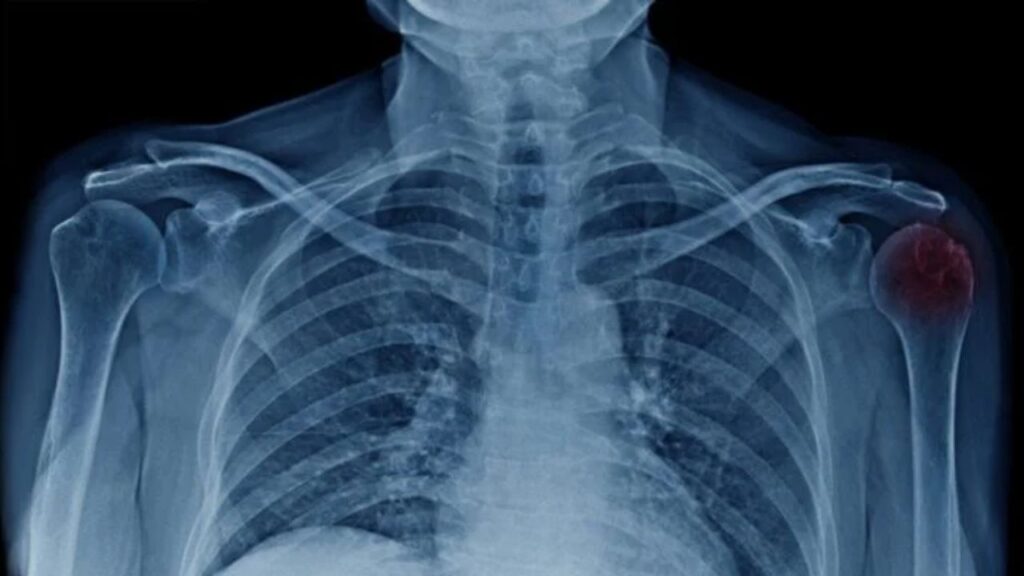

A “bursa” é uma pequena bolsa cheia de líquido que atua como uma almofada entre os ossos e os tecidos moles (músculos e tendões), reduzindo o atrito durante o movimento. No ombro, a bursa subacromial fica logo abaixo da ponta do osso do ombro. Quando essa estrutura fica irritada e inflamada, ela aumenta de volume e causa dor, caracterizando a bursite. Frequentemente, ela está associada a outra condição, a tendinite, formando um quadro de inflamação conjunto.

O diagnóstico é realizado pelo ortopedista através da história clínica e do exame físico, onde manobras específicas provocam a dor típica da bursite. Para descartar outras lesões, como rupturas de tendões ou calcificações, e confirmar a presença de líquido na bursa, o médico geralmente solicita exames de imagem, sendo a ultrassonografia e a ressonância magnética os mais utilizados pela sua precisão.